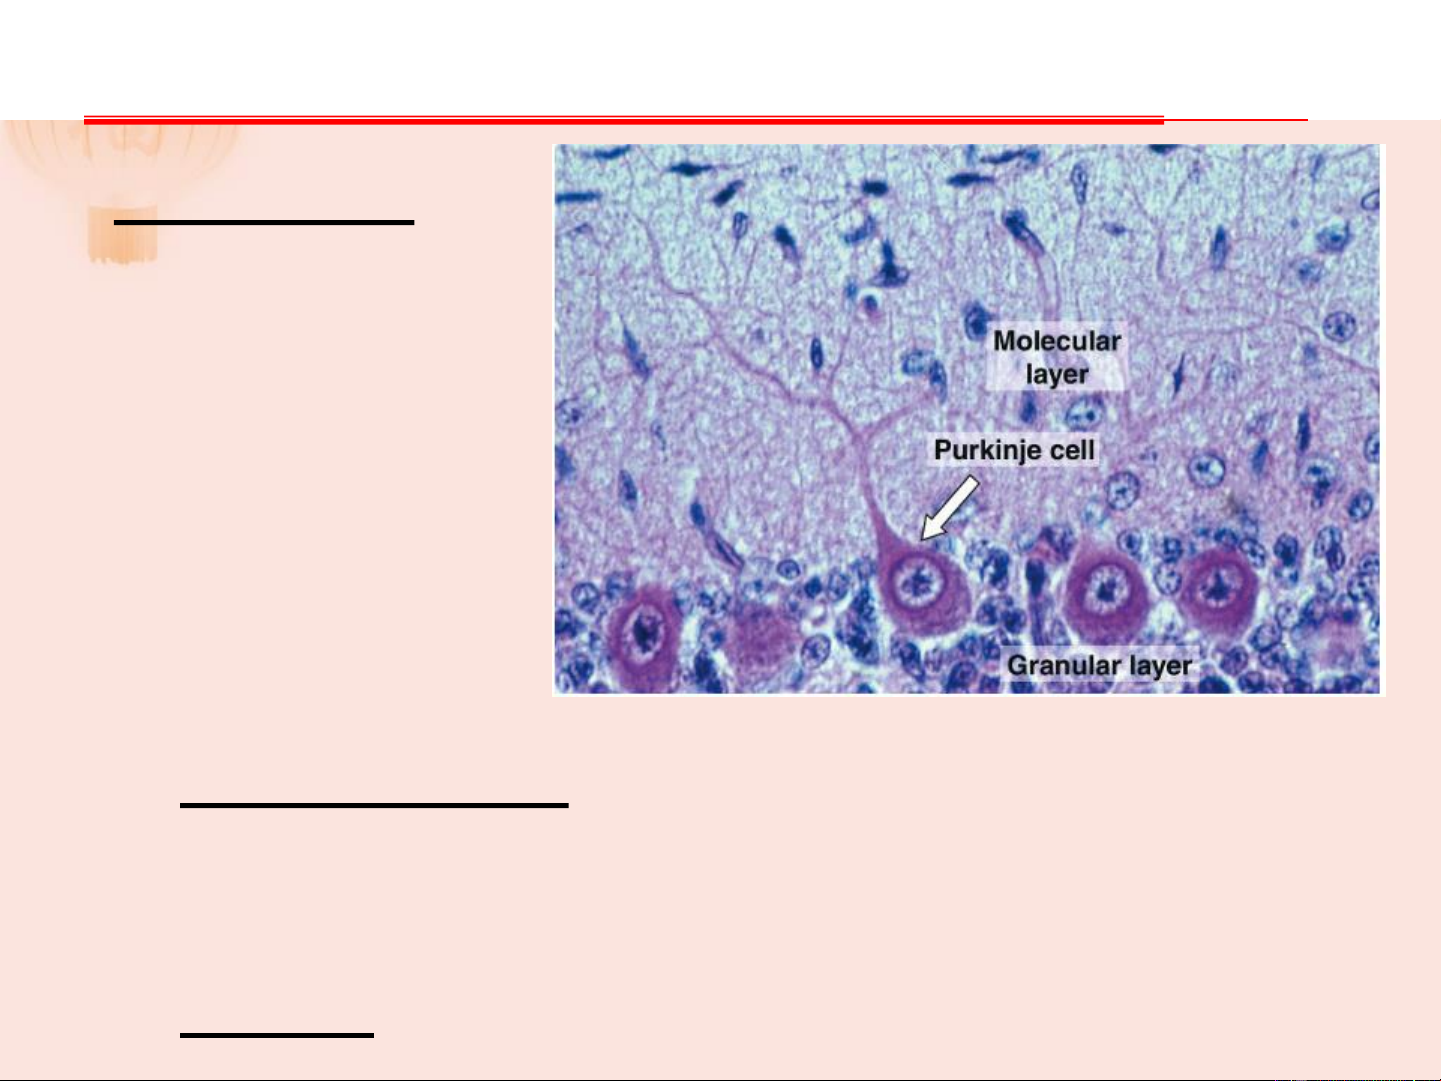

- Chất trắng: gồm những sợi TK có myelin VỎ TIỂU NÃO Lớp phân tử: Thân nơron nhỏ, sợi TK không myelin, TB giỏ, TB sao. Sợi trục TB giỏ ôm lấy TB Purkinje

Lớp TB Purkinje: TB hình trái lê, sợi nhánh hướng về

lớp phân tử, sợi trục xuyên qua lớp hạt vào chất trắng, tận

hết ở nhân răng. Chỉ gồm 1 hàng tế bào, tế bào đặc trưng, kích thước lớn.

Lớp hạt: nhiều nơron nhỏ, đa cực VỎ TIỂU NÃO VỎ TIỂU NÃO VỎ TIỂU NÃO